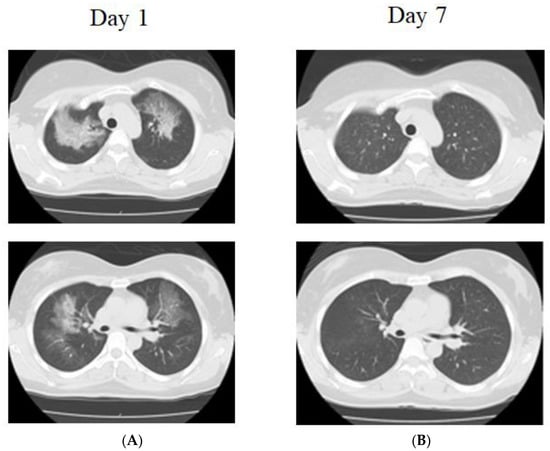

The CT scan revealed that frosted shadows, mainly in both the upper lung fields and peripheral areas, were absent (Figure 2). She had a 5-pack-year history of cigarette smoking for 20 years. The laboratory data revealed leukocytosis (16,900/μL) with neutrophilia (93.5%). The C-reactive protein level was 0.61 mg/dl, and the serum lactate dehydrogenase concentration level rose to 398 IU/L (normal range: 275–512 IU/L). The serum Krebs von den Lungen (KL)-6 level was 239 U/mL (normal range: <500 U/mL). The percentage of macrophages in BALF (Day 5) was 96%. She did not take steroids. One week later, the shadows improved on the CT scan (Figure 2). Two patients were suspected to have WALI based on the radiological findings and anamnesis. However, other diseases, such as infection and eosinophilic pneumonia, were also considered and bronchoscopy was performed and the possibility of other diseases was ruled out.

Figure 2. Chest X-ray and chest computed tomography (CT) in case 2. (A) Bilateral diffuse, ground-glass opacity predominates in the upper lung fields, with a partially mosaic pattern, and no pleural nadir shadow. There is no pleural effusion (Day 1). (B) Improved completely (Day 7).